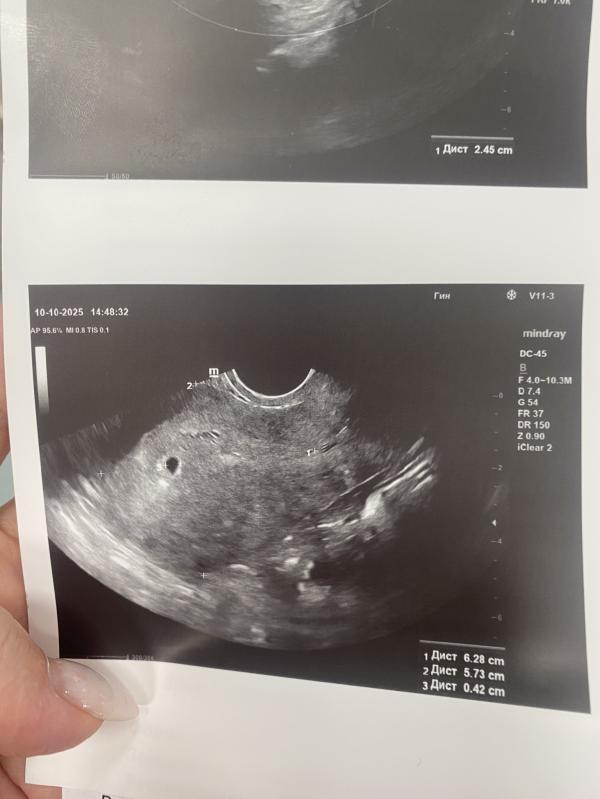

Первое УЗИ при беременности: когда видно плодное яйцо

Вот она бусинка 🥰Расти🙏

Сначала ничего не увидели ( при хгч 48) , как стал хгч 1700 -визуализировали плодное яйцо🫶🏻 26 октября иду на узи, смотреть динамику🙏